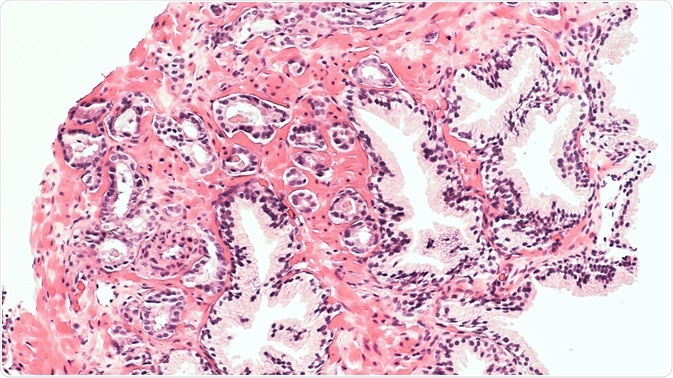

Prostate cancer TMAs were subjected to digital imaging and then the images were scored either visually or by digital analysis for ERβ2 staining in the tumor epithelium. The images for visual scoring were created by scanning the stained slides using an automated Tissuefax microscope (TissueGnostics, Tarzana, CA) and then were reviewed with the help of an online web gallery.

The ERβ2 staining was scored according to the individual TMA spots by a pathologist who had been blinded to the clinical features. The images were analyzed twice independently to assess the reproducibility of visual scoring. The image analysis data was then analyzed further to look for any significant association with the recurrence-free survival period as well as the disease-specific survival after radical prostatectomy.